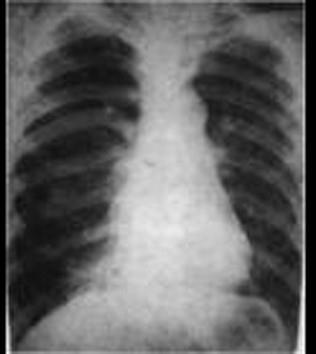

下列哪张图片是脓胸X线表现 ( )A、B、C、D、

问题 下列哪张图片是脓胸X线表现 ( )

选项 A、 B、 C、 D、

答案 B